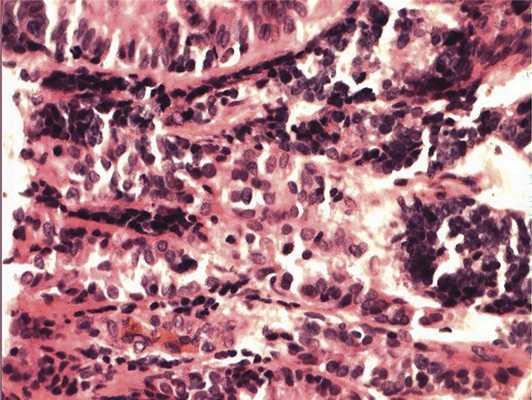

Отмечалось наличие ленточных структур из низкодифференцированных эпителиальных клеток (рис. 4). Параллельно встречались участки солидного строения из клеток с гиперхромными ядрами с признаками клеточного и ядерного полиморфизма. В них почти исчезает строма, появляются митозы, встречаются участки дистрофии и некроза (рис. 5). Опухоль врастает в ткань ДЗН с переходом за laminacribrosa, но не достигает линии отсечения (рис. 6). В таком виде опухоль обладает местнодеструирующим характером роста и может давать метастазы, глубоко инфильтрируя прилежащую к ДЗН ткань хориоидеи. Окончательный гистологический диагноз: злокачественная медуллоэпителиома центрального отдела сетчатки с вовлечением ДЗН и инвазией перипапиллярной хориоидеи, с глубоким прорастанием по зрительному нерву, не достигая линии отсечения.

Рис. 4. Формирование полос из низкодифференцированных нейроэпителиальных клеток. Окраска гематоксилином и эозином. Ув. 400.

Рис. 5. Зоны солидного роста опухоли. Клеточный полиморфизм с фигурами митозов. Окраска гематоксилином и эозином. Ув. 400.